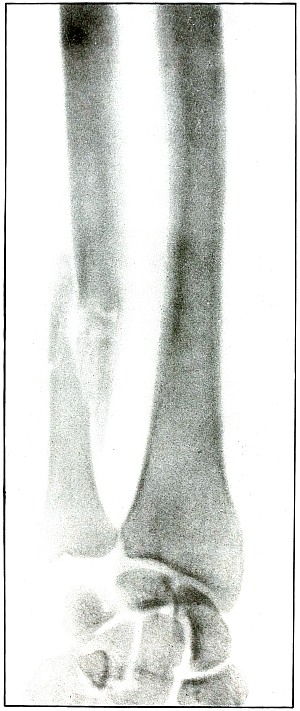

29. Gunshot fracture, radius, lower end 68

30. Gunshot fracture, radius, lower end 70

31. Gunshot fracture, radius, lower end 72

32. Gunshot fracture, ulna 74